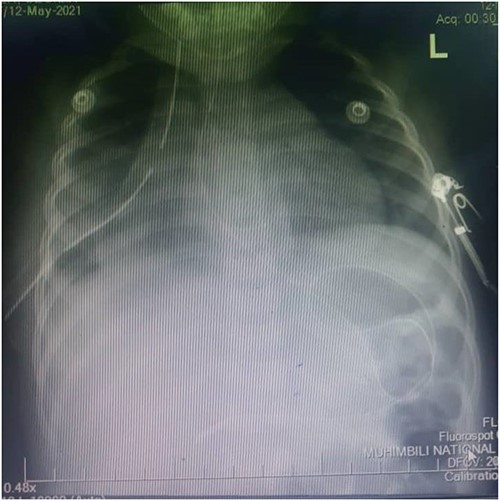

Thus, the tube thoracostomy with under water seal drainage was performed and supportive oxygen therapy was initiated accordingly. In the second day postadmission, the respiratory symptoms resolved and she was weaned off oxygen and other supportive therapies were reduced. Later a whole-body CT scan was performed and admitted in Paediatric Surgery ward in Muhimbili National Hospital. The CT scan revealed a hypodense fluid collection on the right hemithorax, 33HU associated with ipsilateral pulmonary atelectatic changes, discontinuity of the right hemidiaphragm with intrathoracic herniation of the liver that appeared to be normal in size. Nevertheless, the child was in good condition, without respiratory distress or bowel obstruction.

Figures 2 and 3 axial views of thoraco-abdominal CT image taken before laparotomy revealing a ruptured diaphragm of a 1-year-old post trauma patient with reduced right lung volume of expansion.